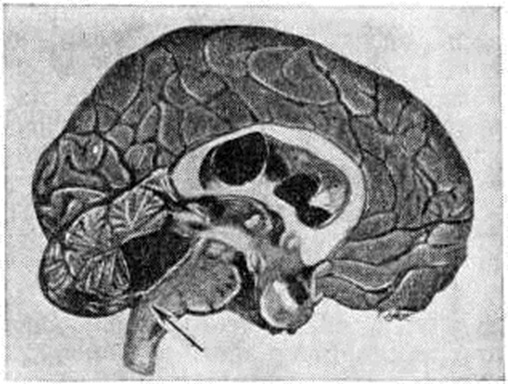

ГидроцефалияГидроцефалия (hydrocephalus; греческий hydor вода + kephale голова; синонимы водянка головного мозга) — состояние, характеризующееся избыточным накоплением цереброспинальной жидкости в желудочках мозга и подоболочечных пространствах. Гидроцефалия является следствием различных заболеваний или травм головного мозга и его оболочек. КлассификацияНаибольшее распространение в СССР получила классификация, предложенная А. А. Арендтом в 1948 год. В ней Гидроцефалия рассматривается в зависимости от времени возникновения, течения, этиологического факторов, локализации и характера нарушения функции ликворного аппарата. По времени возникновения различают врождённую и приобретённую Гидроцефалия, по течению — острую и хроническую. По локализации выделяют наружную и внутреннюю Гидроцефалия При наружной Гидроцефалия имеется избыточное скопление цереброспинальной жидкости преимущественно в субарахноидальных пространствах, при внутренней — в желудочках головного мозга. Нередко наблюдается комбинация внутренней и наружной Гидроцефалия — так называемый общая Гидроцефалия По характеру нарушения функции ликворного аппарата принято различать открытую (сообщающуюся) и закрытую (окклюзионную) Гидроцефалия Открытую Гидроцефалия в свою очередь подразделяют на гиперсекреторную, при которой секреция цереброспинальной жидкости значительно повышена, и арезорбтивную, характеризующуюся нарушением её всасывания. При окклюзионной Гидроцефалия имеется нарушение на различных уровнях оттока цереброспинальной жидкости из желудочков в субарахноидальные пространства в результате спаечного процесса, кист, опухолей и так далее. Встречаются смешанные формы Гидроцефалия, когда окклюзия ликворных путей сочетается с нарушением резорбции или секреции цереброспинальной жидкости. Этиология и патогенезРазличные поражения головного мозга и его оболочек могут привести к Гидроцефалия Чаще всего она наблюдается после инфекционных заболеваний (гнойный эпидемический цереброспинальный менингит, вторичные менингиты и менингоэнцефалиты) и черепно-мозговых травм. Кроме того, Гидроцефалия может возникнуть при затруднении оттока крови из полости черепа (патология венозной системы, тромбоз синусов, сдавление рубцами и спайками отводящих вен), при опухолях, а также при гипертензии, заболеваниях почек и паразитарных поражениях головного мозга. Иногда Гидроцефалия возникает в результате аномалии развития головного и спинного мозга (недоразвитие мозга, мозговые и спинномозговые грыжи и так далее). Вышеперечисленные причины могут привести к нарушению секреции, всасывания или циркуляции цереброспинальной жидкости с последующим развитием Гидроцефалия Патологическая анатомияМорфологически изменения в мозге и оболочках при Гидроцефалия зависят как от основного заболевания, приведшего к Гидроцефалия, так и от длительности повышенного внутричерепного давления. Как правило, наблюдается расширение полостей желудочков, особенно боковых, за счёт увеличения в них количества цереброспинальной жидкости (рисунок 1). Боковые желудочки расширены симметрично как при открытой, так и закрытой Гидроцефалия с окклюзией межжелудочковых отверстий водопровода мозга и апертур IV желудочка (рисунок 2—4). |

Асимметричное расширение желудочков чаще всего наблюдается при закупорке одного межжелудочкового отверстия или на стороне травмы. Прогрессирующее увеличение желудочков приводит к атрофии мозговой ткани, уплощению извилин и сглаживанию борозд мозга. Рано поражаются пирамидные пути. Изменению подвергается прежде всего белое вещество, мозолистое тело и свод. Изменение серого вещества наблюдается при Гидроцефалия в результате травмы и в тяжёлых случаях Гидроцефалия. При врождённой Гидроцефалия может нарушаться строение коры. Атрофия нервной ткани при Гидроцефалия, по мнению У. Пенфилда и Элвиджа (A. Elwidge, 1932), Б. Н. Клосовского (1949), В. П. Пурина (1968), происходит в результате сдавления капилляров мозга вследствие внутричерепной гипертензии. Выраженная астроцитарная реакция в белом веществе при Гидроцефалия является плохим прогностическим признаком. Кроме изменений со стороны ткани мозга, при Гидроцефалия отмечают выраженные изменения и со стороны сосудистых сплетений, эпендимы желудочков и его оболочек. Наблюдается атрофия сосудистых сплетений с фиброзным перерождением их соединительнотканной основы и гибелью эпителия. При Гидроцефалия после инфекционных заболеваний выявляют признаки гранулематозного эпендиматита (смотри Хориоэпендиматит). Мозговые оболочки резко утолщены, мутны, отёчны. Отмечают их фиброз, сращение главным образом в области базальных цистерн основания мозга, большого затылочного отверстия и апертур IV желудочка. В оболочках выявляют воспалительные инфильтраты. При травматической Гидроцефалия в мозге находят следы бывших кровоизлияний, рубцы в местах некрозов мозговой ткани, спайки в области путей оттока цереброспинальной жидкости и так далее. В сосудах головного мозга при Гидроцефалия обнаруживают признаки артериосклероза с гиалинозом сосудов.

Рисунок 3. | ||